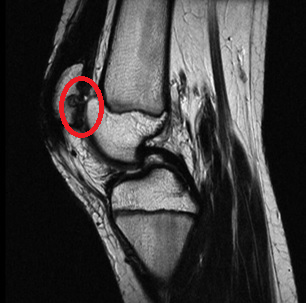

Для диагностики применяют рентген и томографию.

Первый показывает состояние костной ткани, вторая – помогает сведениями о мягких тканях колена.